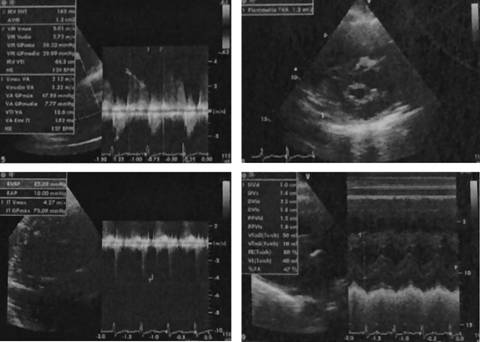

Puérpera de 32 años con antecedente de dos embarazos previos complicados. El primero, con preeclampsia severa con muerte del feto in utero por causa desconocida a las 38 semanas de gestación; el segundo embarazo cursó normoevolutivo durante la gestación hasta el expulsivo donde se realizó un parto instrumentado con fórceps. Inició siete días previos a su ingreso con edema de miembros pélvicos no doloroso, ascendente, caliente, blando; a las 24 horas se agregó cefalea parietal bilateral, pulsátil, con intensidad 8/10, acompañada de náusea con vómito de contenido gastrobiliar y disnea de pequeños esfuerzos. Acudió a facultativo, quien detectó cifras tensionales de 130/80 y la refirió a un hospital de tercer nivel. Se internó en el Servicio de Materno-Fetal con sospecha diagnóstica de trombosis venosa profunda. Cursó con deterioro súbito de la función pulmonar manifestado con hipoxemia severa; requirió de ventilación mecánica invasiva por desarrollo de edema agudo pulmonar; por taller hemodinámico se documentó falla cardiaca con datos de disfunción diastólica, que precisó de inotrópico y vasopresores. Se recibió en la terapia intensiva sedada con RAMSAY 5, eutérmica (temperatura: 37.5 oC), taquicárdica (122 latidos/minuto), hipotensa (89/47 mmHg), aún con apoyo de vasopresina y norepinefrina, manteniendo presiones medias > 70 mmHg. Con precordio hiperdinámico con levantamiento para esternal bajo, se palpó chasquido de cierre pulmonar. Ruidos cardiacos disminuidos con reforzamiento del segundo ruido y soplo holosistólico II/VI en el foco mitral, sin galope o frote pericárdico; trazo electrocardiográfico: con fibrilación auricular de respuesta ventricular alta (Figura 1), taller hemodinámico con patrón hiperdinámico. Con soporte ventilatorio mecánico invasivo, campos pulmonares hipoventilados con estertores en velcro, abdomen globoso con aumento del timpanismo, peristaltismo disminuido, con oliguria en 0.3 cm3/kg/hora. Se realizó una radiografía de tórax con infiltrado en alas de mariposa, además de cono pulmonar prominente, elevación del hemidiafragma derecho (Figura 2). Laboratorios: antiestreptolisinas 53 UI/m, factor reumatoide 20.5, procalcitonina 4.120 ng/mL, CPK 281 µ/L, CKmb 29 U/l, dímero D 9898 ng/mL, péptido natriurético cerebral: 863.90 pg/mL, velocidad de eritrosedimentación y proteína C reactiva aumentadas. Se realizó interconsulta con el Servicio de Cardiología, quien llevó a cabo ecocardiograma transtorácico, con estenosis valvular mitral con área de 1.2 cm (Figura 3) y gradiente transvalvular de 36 mmHg, con probable etiología reumática. Hipertensión arterial pulmonar severa con presión sistólica del ventrículo derecho (PSVD) de 83 mmHg y función sistólica biventricular conservada; dilatación del ventrículo derecho con excursión sistólica del anillo tricuspídeo (TAPSE) de 23 mm; no se pudo evaluar de forma adecuada el estado de la válvula aórtica, solo se encontró gradiente ligeramente incrementado, que se puede atribuir a hiperdinamia. Sin signos clínicos de tromboembolia pulmonar, fracción de expulsión del ventrículo izquierdo (Fevi) de 80% (Figura 4). El Servicio de Nefrología integró el diagnóstico de lesión renal aguda prerrenal AKIN III y el Servicio de Neumología corroboró ausencia de datos de trombosis pulmonar, aun con la elevación del dímero D (9898). Se instauró manejo farmacológico con vasodilatadores dinitrato de glicerilo, inotrópico (levosimendam), morfina, diuréticos, betabloqueador, sildenafil (para manejo de hipertensión pulmonar) y terapia de sustitución renal precoz (hemodiálisis) de urgencia para manejo de sobrecarga hídrica. La paciente evolucionó favorablemente a la terapéutica a base de metas de paciente crítico. Se inició el retiro de aminas vasopresores, sildafenil e inotrópico a las 72 horas, sin repercusión hemodinámica, con posterior retiro de la ventilación mecánica al cuarto día de resolver el edema pulmonar. Con mejoría hemodinámica, se realizó una nueva valoración por parte del Servicio de Cardiología, quien la catalogó como estenosis mitral moderada y decidió control ambulatorio. La paciente fue egresada de terapia al octavo día de internamiento, sin repercusión hemodinámica o fallas orgánicas. A la semana inició consulta de forma ambulatoria en el Servicio de Cardiología para programar su tratamiento quirúrgico: valvuloplastia percutánea mitral por balón.

Las mujeres con estenosis mitral a menudo presentan sintomatología durante el embarazo por el aumento del volumen sanguíneo, el gasto cardiaco y la frecuencia cardiaca.7,8 Sin embargo, como explicamos previamente, mucha de la sintomatología asociada puede ser confundida con aquella propia del embarazo, sobre todo en los casos de estenosis leves.1,3,6 Se reporta que las complicaciones cardiacas asociadas al embarazo están en relación con el grado de severidad de la estenosis; por lo tanto, en una estenosis moderada (1-1.5 cm2) se observarán complicaciones en 67% de las pacientes (Tabla 2).8 En este caso en particular, llama la atención que tuvo como antecedente un embarazo de término que no presentó manifestaciones durante su desarrollo o en el puerperio; se infiere que el uso de fórceps en el periodo expulsivo disminuyó el esfuerzo durante el nacimiento y retardó las manifestaciones de inestabilidad hemodinámica hasta la siguiente etapa de riesgo, el puerperio.5 El aumento de la presión auricular izquierda se transmitió de forma retrógrada a la vasculatura pulmonar y a las cavidades derechas, ocasionando edema pulmonar e hipertensión pulmonar y arritmia.3,9 Que la paciente presentara los datos de falla cardiaca derecha durante su internamiento y su ingreso temprano a la terapia intensiva ayudaron a mejorar su pronóstico de supervivencia; sin embargo, en pacientes de las mismas características, es muy importante para el diagnóstico la anamnesis y la exploración clínica durante el control prenatal, ya que los signos auscultatorios permiten la sospecha. Otras pruebas complementarias utilizadas son el electrocardiograma, en el que se puede ver cómo en una estenosis mitral con ritmo sinusal las ondas P suelen sugerir el crecimiento de la aurícula izquierda. Cuando existe hipertensión pulmonar grave o insuficiencia tricuspídea que complica la estenosis mitral y produce crecimiento de la aurícula derecha, la onda P puede volverse alta y acuminada en la derivación II y positiva en la derivación V1; en el caso presentado observamos en el electrocardiograma fibrilación auricular secundaria a la dilatación de la aurícula derecha por aumento en la postcarga del VD (Figura 1). En la paciente, a pesar de tener un control prenatal aceptable durante las consultas, se obvió la auscultación de los ruidos cardiacos; por lo tanto, al no haber sospecha clínica ni por antecedentes, no se hicieron estudios dirigidos hacia la patología cardiaca. El embarazo en alguien con estenosis mitral debe considerarse de alto riesgo y, por tanto, precisa un seguimiento estricto, tanto obstétrico como cardiológico, cada dos semanas. La medida más importante para disminuir la sintomatología es el reposo. Además, se debe seguir una dieta sin sal, hipocalórica y rica en hidratos de carbono. El tratamiento farmacológico debe hacerse con diuréticos, teniendo en cuenta que puede disminuir el flujo uteroplacentario en pacientes con problemas hemodinámicos, condicionando muerte fetal. El abordaje con digital y heparina cálcica subcutánea debe valorarse en casos de fibrilación auricular. La hospitalización se aconseja en enfermas con estenosis moderadas o severas.5 El tratamiento quirúrgico debe considerarse en aquellas con sintomatología invalidante o cuando el área valvular sea menor o igual a 1.5 cm (Tabla 2).5,8